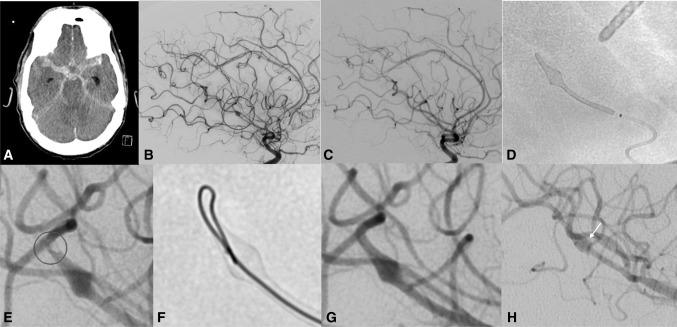

Eight patients were identified. The mean interval between aSAH and FD was 6 days. Of the eight ruptured aneurysms, one was blister-like, one saccular, one mycotic, and the remaining five were dissecting aneurysms. Intraprocedural transient thrombus formation was observed in four patients (50%). Stent thrombosis was observed in one patient (12.5%) on day 3 with spontaneous recanalization after being switched onto DAPT. None of the aneurysms rebled after treatment. Two patients died due to cerebral vasospasm. Complete aneurysm occlusion had been achieved in all but one patient at angiographic follow-up (average 6 months).

共确定了 8 例患者。aSAH 与 FD 的平均间隔为 6 天。8 个破裂的动脉瘤中,1 个为泡状,1 个为囊状,1 个为真菌性,其余 5 个为夹层动脉瘤。4 例(50%)患者术中观察到短暂血栓形成。1 例患者(12.5%)在第 3 天出现支架内血栓形成,在改用 DAPT 后自发再通。治疗后无动脉瘤再出血。2 例患者因脑血管痉挛死亡。血管造影随访时,除 1 例患者外,所有患者的动脉瘤均完全闭塞(平均随访 6 个月)。